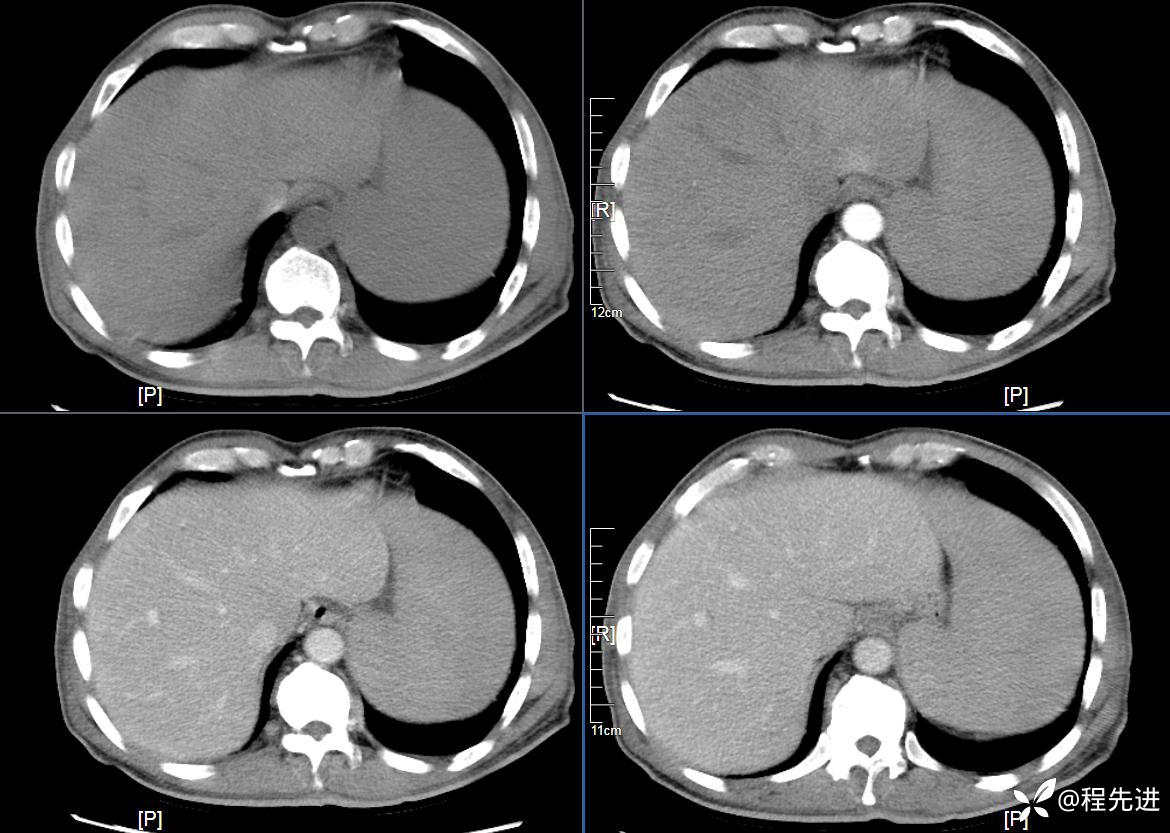

患者性别:男

患者年龄:59岁

简要病史:体检发现脾脏肿大半月

CT平扫及增强3期: